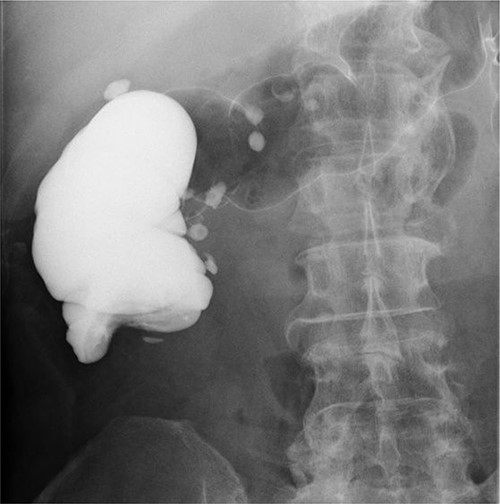

A 59-year-old man was followed up for a year by a dermatologist for psoriasis vulgaris. During this time, he suffered repeated occurrences of cecal diverticulitis diagnosed by contrast-enhanced computed tomography (CT) and was referred to our department for detailed examination and treatment. On examination, he had symptoms associated with subileus such as abdominal distension and pain. Colonoscopy showed a mass with circumferential stenosis in the ascending colon. The surface of the mass showed vascular congestion without malignant findings (Fig. 1a,b). An endoscope could not pass through the stenosis, and enema colonography showed complete stenosis (Fig. 2). Contrast-enhanced CT/magnetic resonance imaging (MRI) revealed a thick wall from the ileocecal region to the ascending colon, which was accompanied by a ring-shaped, layered appearance of mucosal and muscular layers (Fig. 3a–c).

Lower gastrointestinal endoscopy showed a mass with circumferential stenosis in the ascending colon (a), and its surface showed vascular congestion without malignant findings (b).